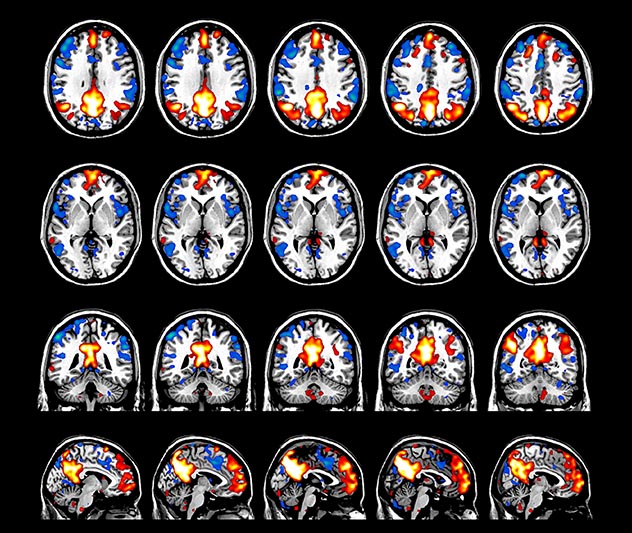

Imaging was performed using Ingenia 3T CX with a 32ch dS Head coil, TR 1.6 sec, TE 35 ms, voxel size 3.1 x 3.1 x 3.1 mm, 46 slices and Multiband SENSE factor 2. Image provided by Dr. Gispert

Default mode network as discovered by resting state fMRI in one participant of the ALFA cohort [7]. rs-fMRI allows us to find networks of brain regions with highly correlated activity and sustaining distinct brain functions. The default mode network (in warm color scale) is active when the brain is focused on introspective thinking and has been shown to be altered in Alzheimer’s. Interestingly, brain areas of this network are known to show abnormal levels of one of the pathological hallmarks of Alzheimer’s (b-amyloid deposition) in preclinical stages. We want to better understand the alterations of these brain networks in preclinical stages of Alzheimer's and explore their potential use as biomarkers.

The fMRI pulse sequence was a single shot FFE echo planar acquisition using MultiBand SENSE factor 5, dS SENSE factor 1.25, isotropic voxel size 2.7 mm, 50 transverse slices, TR 700 ms, TE 30 ms, flip angle 52 degrees, 765 dynamic scans, total scan duration 9:01 minutes. Image provided by Matthan Caan, PhD, Assistant Professor at the AMC.